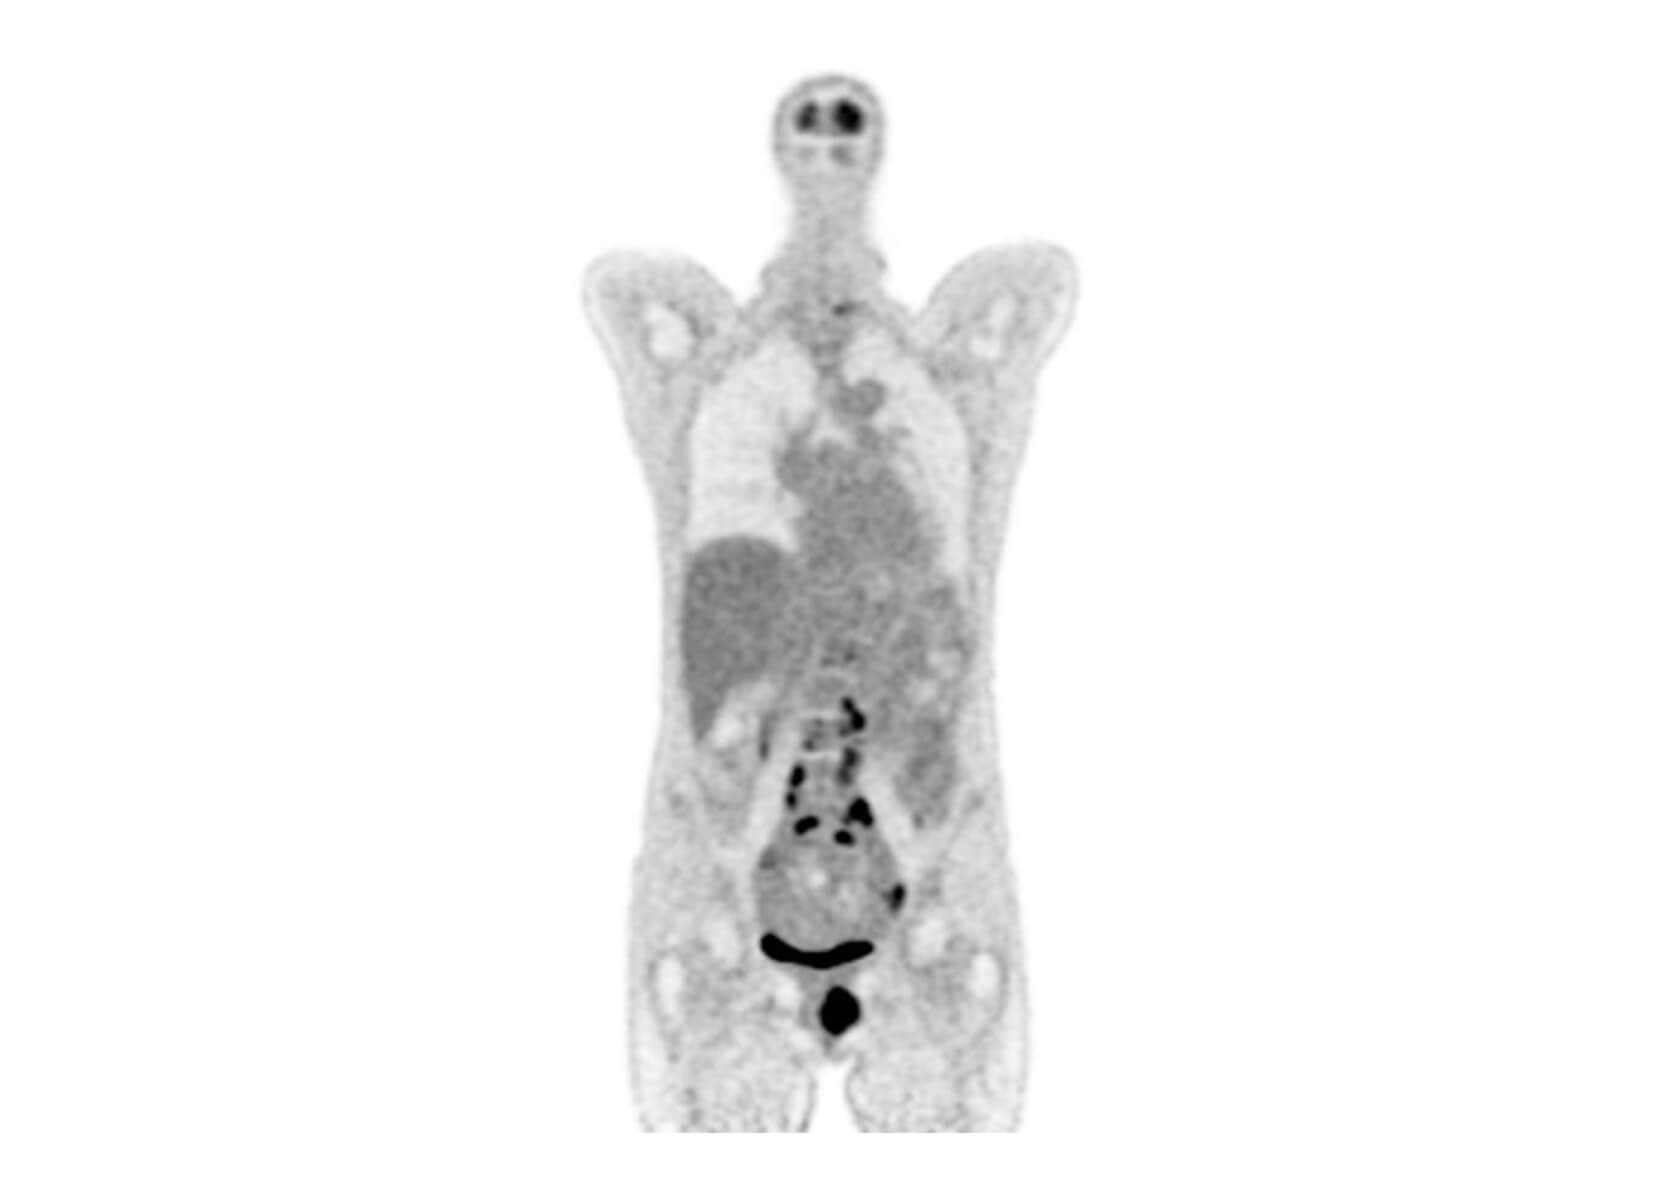

AI-powered image enhancement for low count PET imaging.

Increase patient throughput and improve diagnostic image quality using AI on your existing PET systems.

Upgrade scanner performance

Increase capacity and revenue

Improve patient experience

ROI in weeks

Supports all FDA-approved radiotracers

Vendor-neutral deployment

PET/CT and PET/MR compatible